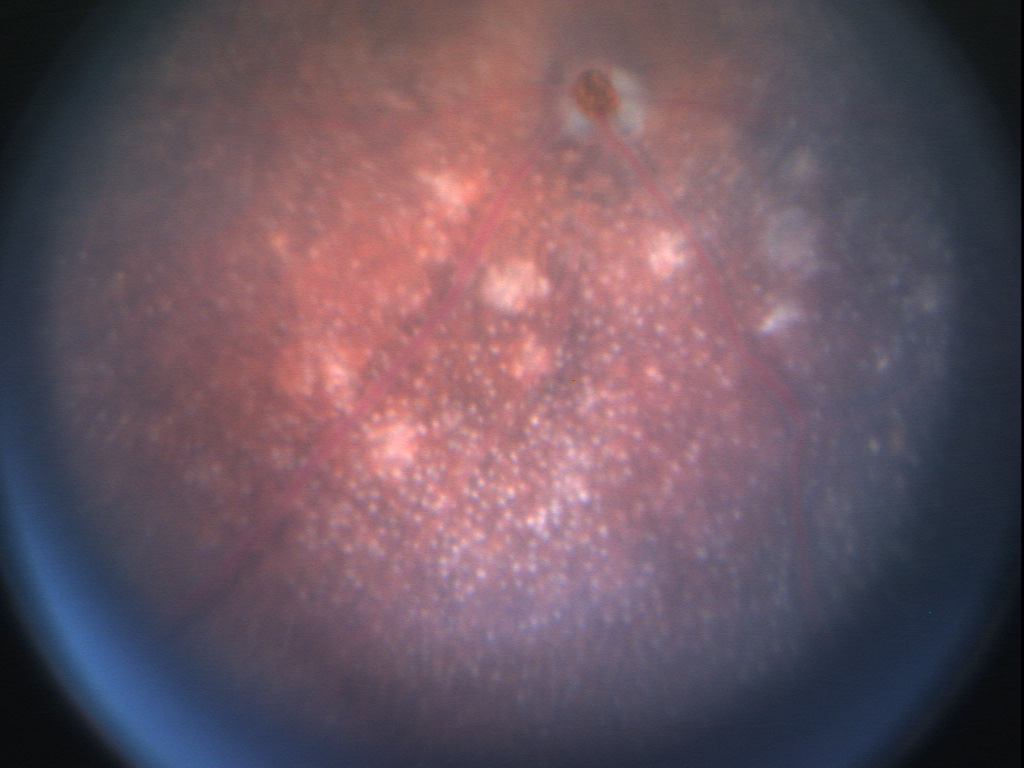

Michelle Cheng shows that inhibition of vascular endothelial growth factor (VEGF) in the retina can promote inflammation by increasing the expression of cell adehesion molecules that enhance extravasation of immune cells from the vasculature. In a paper published in Human Gene Therapy she shows that rAAV mediated expression of a VEGF drug causes retinal vasculitis.